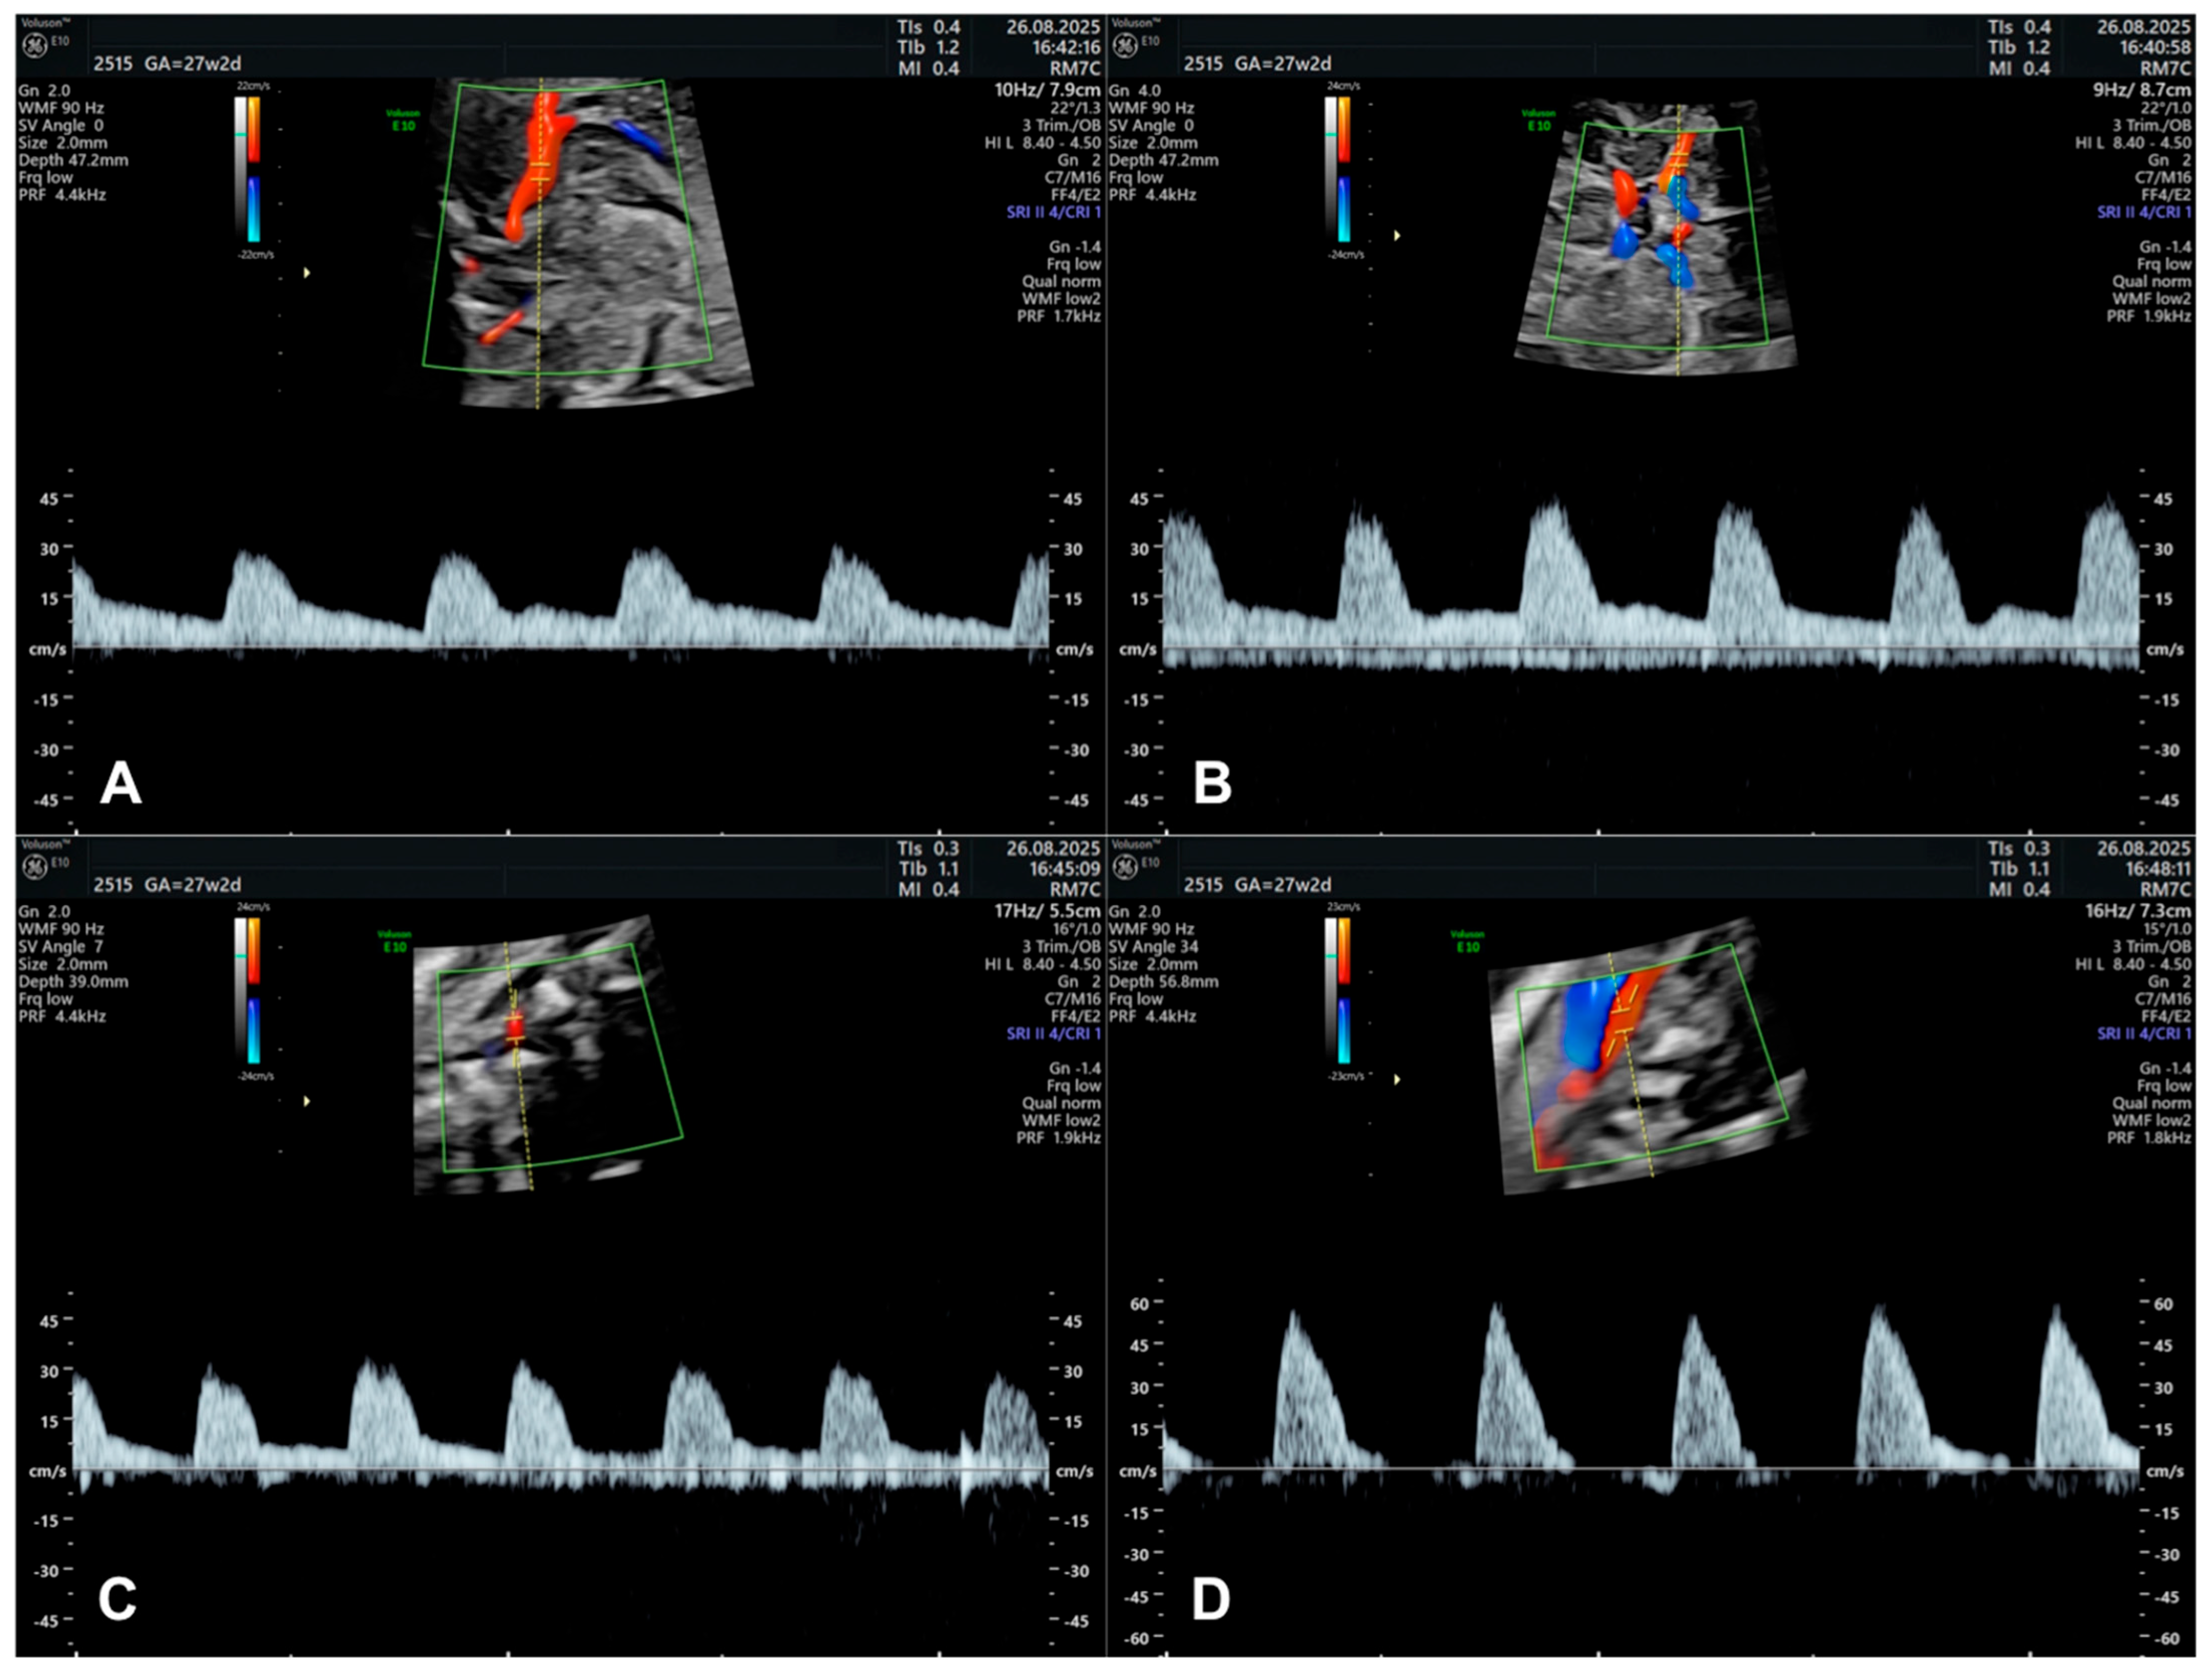

3.7. Doppler Studies of Foetal Cerebral Blood Flow